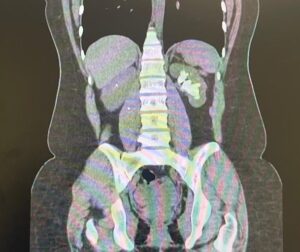

Paciente do sexo feminino, branca, 28 anos comparece ao consultório de especialidade encaminhada após diagnóstico e tratamento de quadro de cistite feito atendimento de emergência com achado em exame de imagem (mostrado abaixo). Foi iniciado tratamento com cefuroxima (500 mg de 12/12h por 5 dias). Negou febre, calafrios, hematúria, disúria, outras infecções do trato urinário (ITU). Refere passado de litíase urinária na infância com necessidade de algumas intervenções, dentre elas: 04 litotripsias extracorpóreas por ondas de choque (LEOC) à esquerda e 02 ureterorrenolitotripsias flexíveis a laser bilaterais.

Exames laboratoriais da emergência mostram leucocitose sem desvio, função renal preservada e discreto aumento de PCR. EAS com piúria e hematúria microscópica.

ACálculo renal coraliforme completo e indicação de ureterorrenolitotripsia flexível associada a nefrolitotripsia percutânea (terapia combinada).

DCálculo renal coraliforme completo e indicação de nefrolitotripsia percutânea (NLPC).